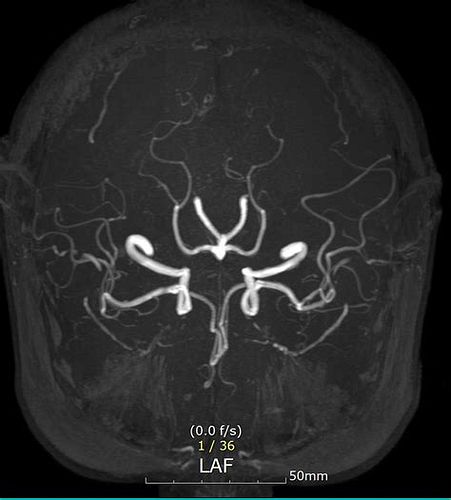

뇌 MRA (뇌혈관 자기공명영상) 검사

- 비급여 기준

- MRI와 유사하게 40만 원 선으로 안내하는 병원 사례 있음.

- 병원마다 차이가 있으니 사전 확인 필요.

MRA 검사 비용

- 비급여(보험 미적용) 기준

- 대학병원: 비조영 MRA 35~60만 원, 조영 MRA 50~80만 원.

- 종합병원: 30~50만 원(비조영), 45~70만 원(조영).

- 영상의학 전문병원: 25~40만 원(비조영), 40~65만 원(조영).

- 지역 의원: 20~35만 원(비조영), 35~55만 원(조영)

- 실제 예시: 포항시 에스포항병원 뇌 MRA 48만 원, 사랑의병원 58만~50만 원(검진시 할인가)